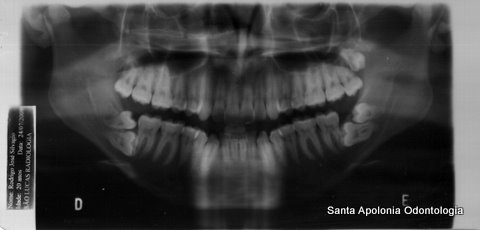

Radiografia Panoramica , com 7 dentes do Sisos!